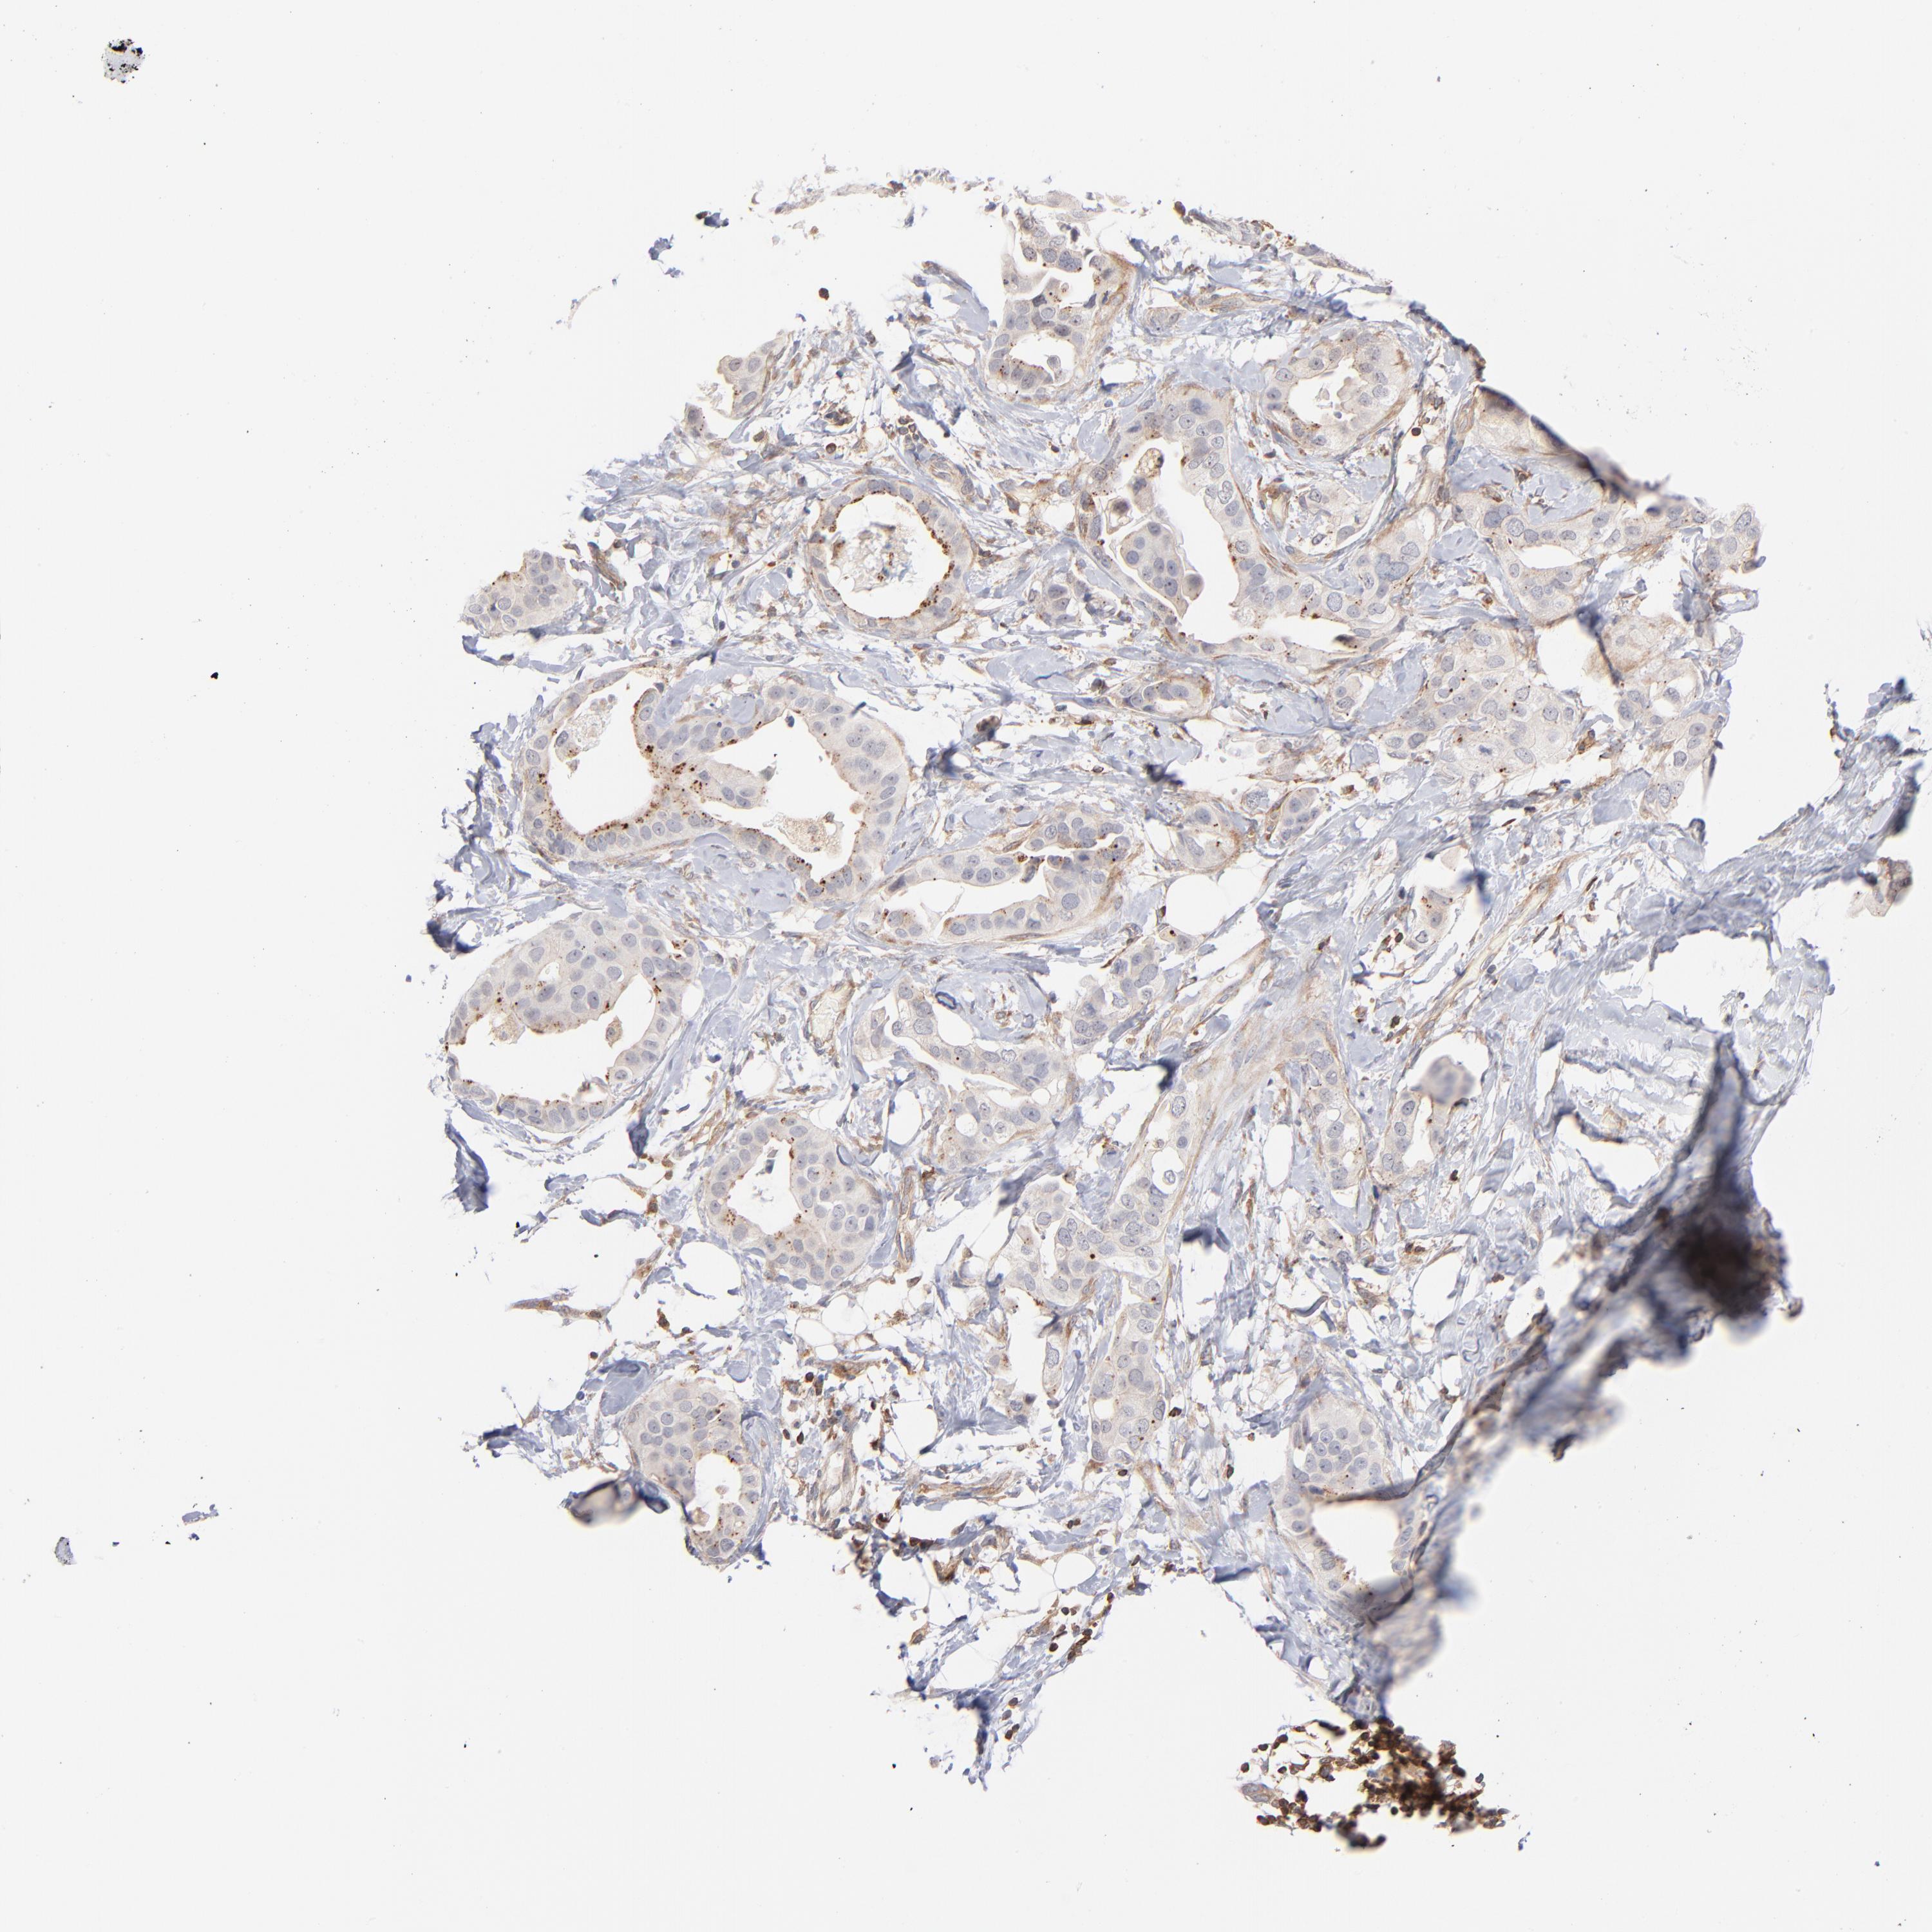

BRCA TCGA BRCA VALIDATION PROTEIN EXPRESSION

ANTIBODIES

AND

VALIDATION